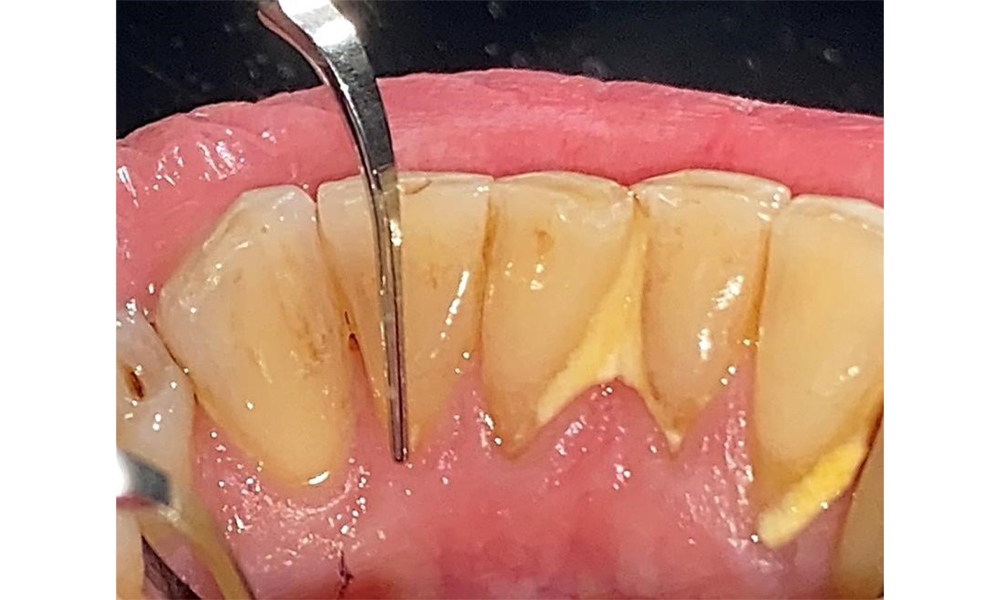

The patient has stage II, grade B periodontitis (5). At 1 to 3 mm, the clinical probing depths were within the physiological range. Localized probing depths of 5 mm were observed on the mesiopalatal aspects on both 17 and 27. There are generalized recessions of 1–3 mm with partial loss of the interdental papillae (Fig. 2, Fig. 3, Fig. 4)

The documentation of periodontal findings, including pocket depth probing and bleeding status, is mandatory during each dental appointment due to the presence of periodontitis (Fig. 8). This will record the individual therapeutic needs and facilitate a rapid response to any progression of the pre-existing periodontitis.

Probing to document the findings in tooth 27 mesiopalatal. © Dr R. Krapf

Fig. 8: Probing to document the findings in tooth 27 mesiopalatal. © Dr R. Krapf

Detailed periodontal findings, including the documentation of pocket depths, bleeding on probing, recessions, furcation involvement and degree of loosening, must be examined annually.